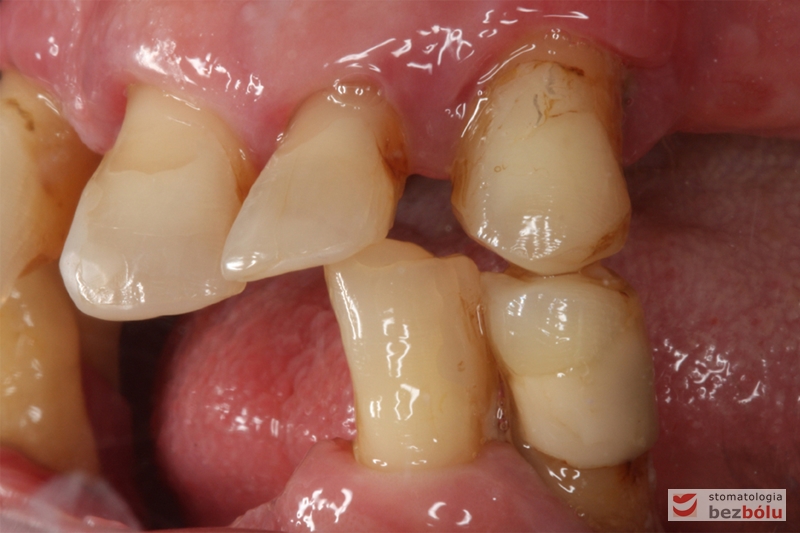

Stan wyjściowy - bez protez, liczne braki zębowe i po 2 nierokujące zęby w szczęce i żuchwie

Stan wyjściowy – bez protez, liczne braki zębowe i po 2 nierokujące zęby w szczęce i żuchwie